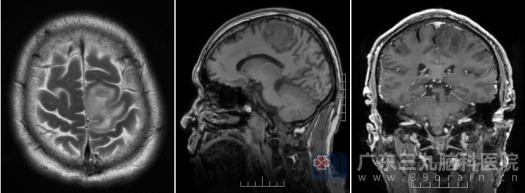

入院后,外十科团队为周大爷进行了详细的检查,真是:不查不知道,一查吓一跳:最近一次的检查结果带来了一个意外的诊断——头颅MR提示,他脑内的异常并非“脑梗死”,而是一个约28×31mm大小的占位性病变,考虑为“胶质瘤”。尽快完善评估和术前准备。随后,在欧阳辉教授和樊雁峰主任医师的带领下成功为他实施了手术,将左侧额叶的肿瘤完整切除。

术前影像资料